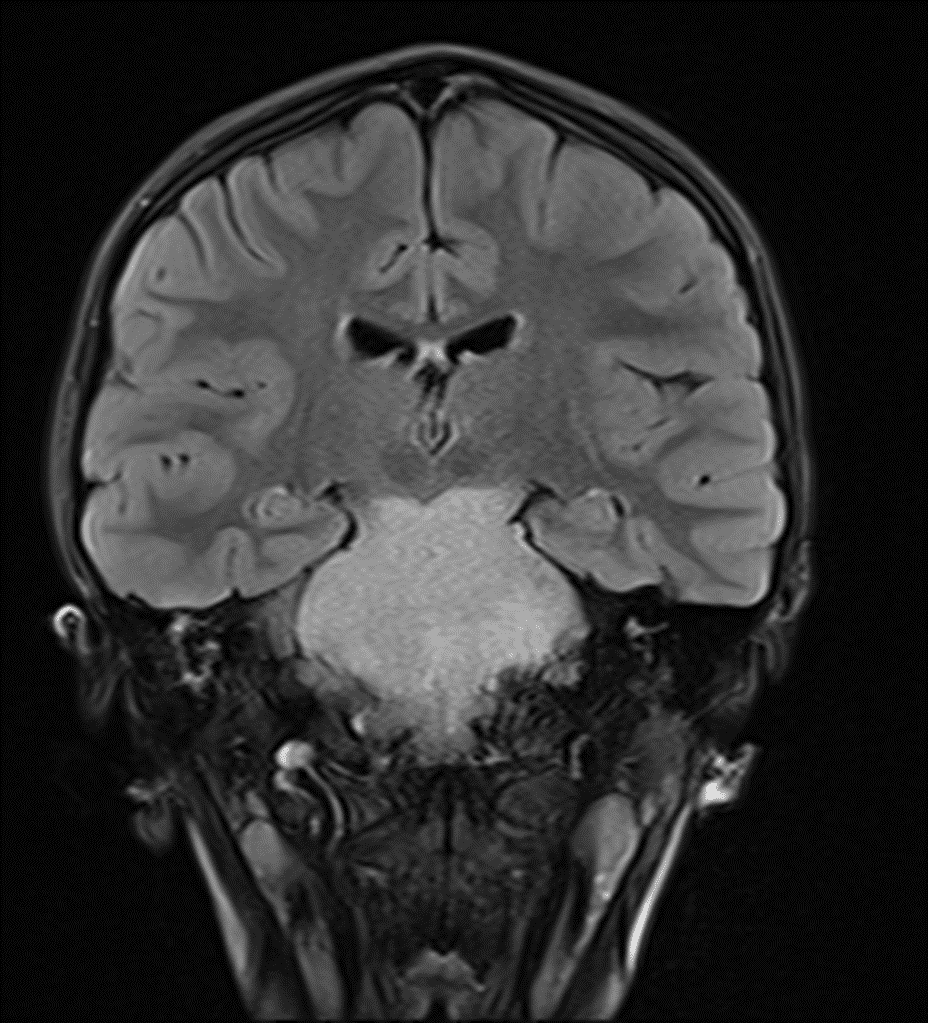

Homogeneous FLAIR hyperintense mass involving the entire pons and extending into the midbrain and medulla, which is a classic imaging appearance for a diffuse midline glioma.